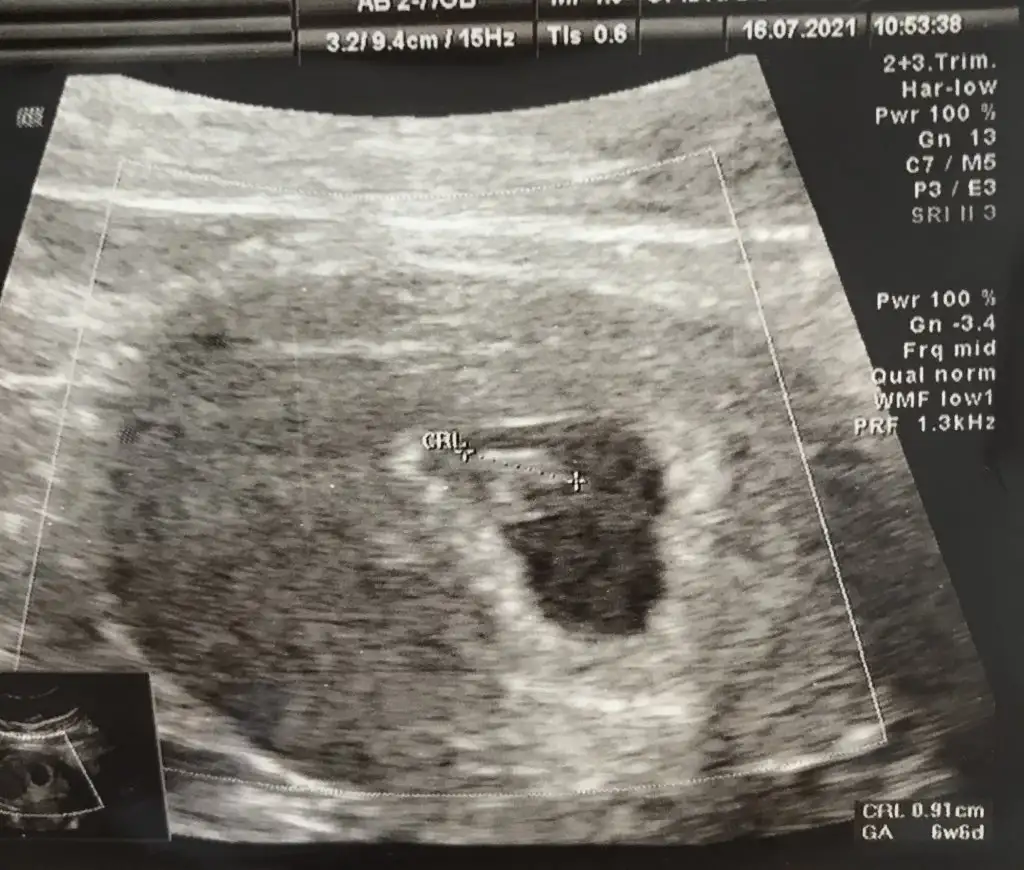

Maşallah Süphanallah. Yerim yaaBuda ilk fotografımız kızlar

kese fasulye değil he yuvarlak gibi kız mı acabaa dedikleri doğru mu kiiBuda ilk fotografımız kızlar

Hayırlı olsun canım. Vajinal ultrason mu goruntuBuda ilk fotografımız kızlar

Normalde daha yuvarlaktı aslında görüntüyü alabilmek için heralde biraz bir köşesinden yamulmuşkese fasulye değil he yuvarlak gibi kız mı acabaa dedikleri doğru mu kii

Yok canım karından çok teşekkür ederimHayırlı olsun canım. Vajinal ultrason mu goruntu